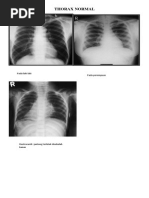

TORAKS PA DAN LATERAL NORMAL

Foto simetris dan inspirasi maksimal

Soft tissue dan skeletal normal.

Trakea masih di tengah.

Cor tidak membesar.

Tidak tampak kalsifikasi aorta/elongatio aorta.

Mediastinum dalam batas normal.

Lokasi bayangan hepar dan gastric bubble dalam batas normal.

Sinuses tajam/tumpul/berselubung dan diafragma

normal/elevasi/mendatar/tenting/scalloping/berselubung.

Pulmo:

- Hili normal/melebar/kabur.

- Corakan bronkovaskuler normal/meningkat/menurun.

- Tidak tampak infiltrat/nodul/massa.

- Tidak tampak perselubungan opak.

- Tidak tampak bayangan lusen.

- Tidak tampak sillhouette sign.

KESAN :

- Tidak tampak TB paru aktif.

- Tidak tampak kardiomegali.

Sinus anterior tajam/tumpul, sinus posterior tajam/tumpul.

Retrosternal space cerah/menyempit.

Retrocardiac space cerah/menyempit.